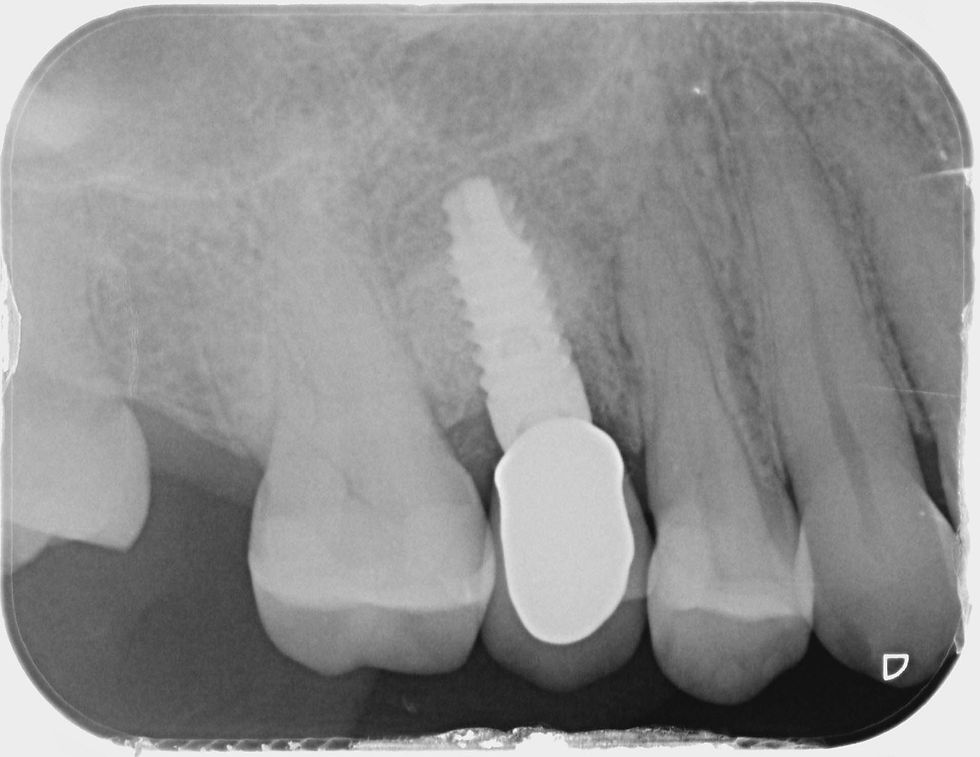

Radiographic image after 1 year from the extraction: peri-implant bone volumes are stable over time.

2 years follow-up. A proper maturation of the peri-implant tissues can be appreciated, with a subsequent optimal aesthetic result. The radiograph confirms the bone volumes maintenance. Physiological probing and negative bleeding indexes are evidence of the excellent peri-implant connective density around the convergent UTM neck of Prama implant.